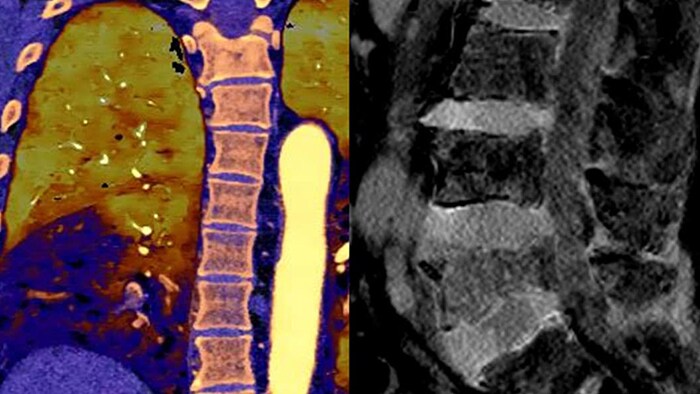

Ahora puede saber fácilmente tanto el "dónde están las cosas" del CT convencional como el "lo que son las cosas" revelado por los datos del detector espectral. Las capas de datos espectrales enriquecidos mejoran la caracterización y la visualización del tejido, y reducen la necesidad de realizar exploraciones de seguimiento en exámenes subóptimos y hallazgos accidentales.

Imagen de CT convencional (izquierda) Imagen de CT con detector espectral (derecha)